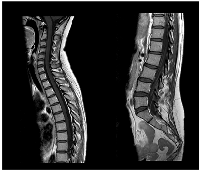

Figure 3

CE MRI response evaluation after 3 cycles of T-DXd.

Right parietal lesion was residual and pachymeningeal infiltration was not found (arrows).

A slow but steady neurological improvement was achieved, with full autonomy recovery after only three cycles of T-DXd. Response evaluation with CE and neuraxis MRI showed excellent disease response: right parietal lesion was residual and pachymeningeal infiltration was not found; LMC was noticeably reduced (in extension and intensity) (Figures 3 and 4). Toraco-abdominal and pelvic CT (TAP-CT) was systematically negative for new distant secondary disease.